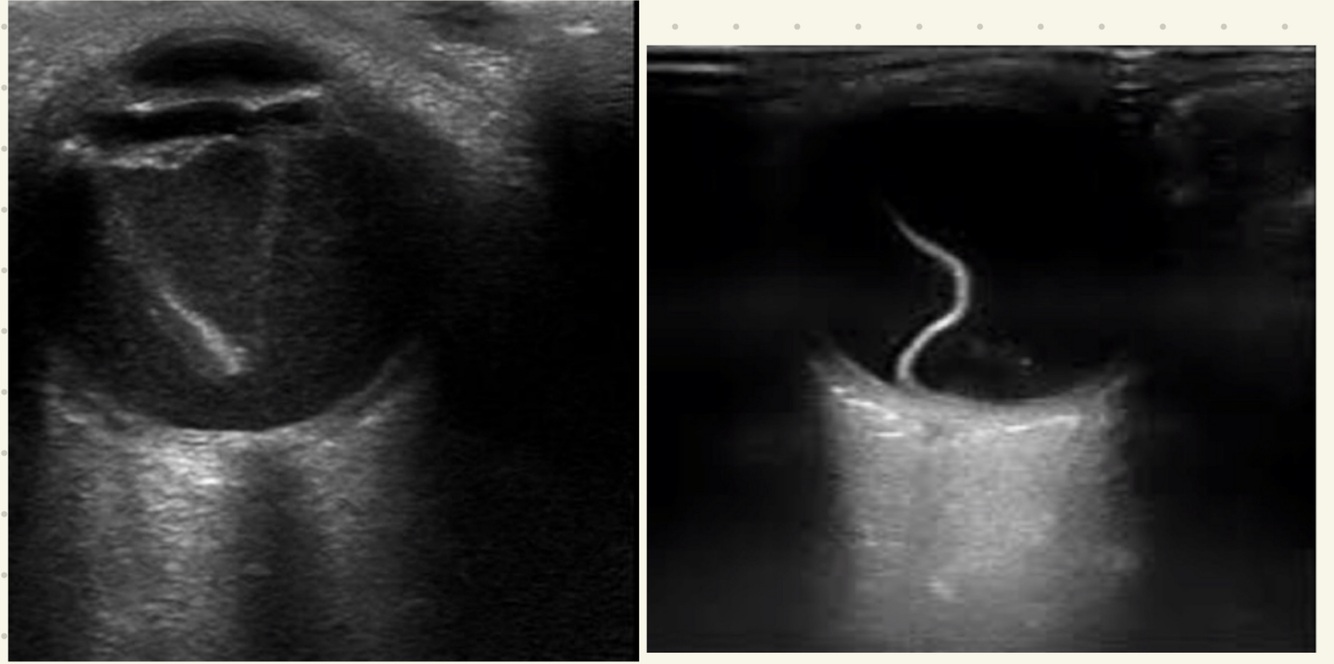

¿Qué se aprecia en RB por USG?

Lesión hiperecogénica con calcificaciones

Hallazgos de USG en deprendimiento de retina:

• Retina doblada y brillante

• Movimientos disminuyen con tiempo

• Forma triangular en humor vítreo (sangre)